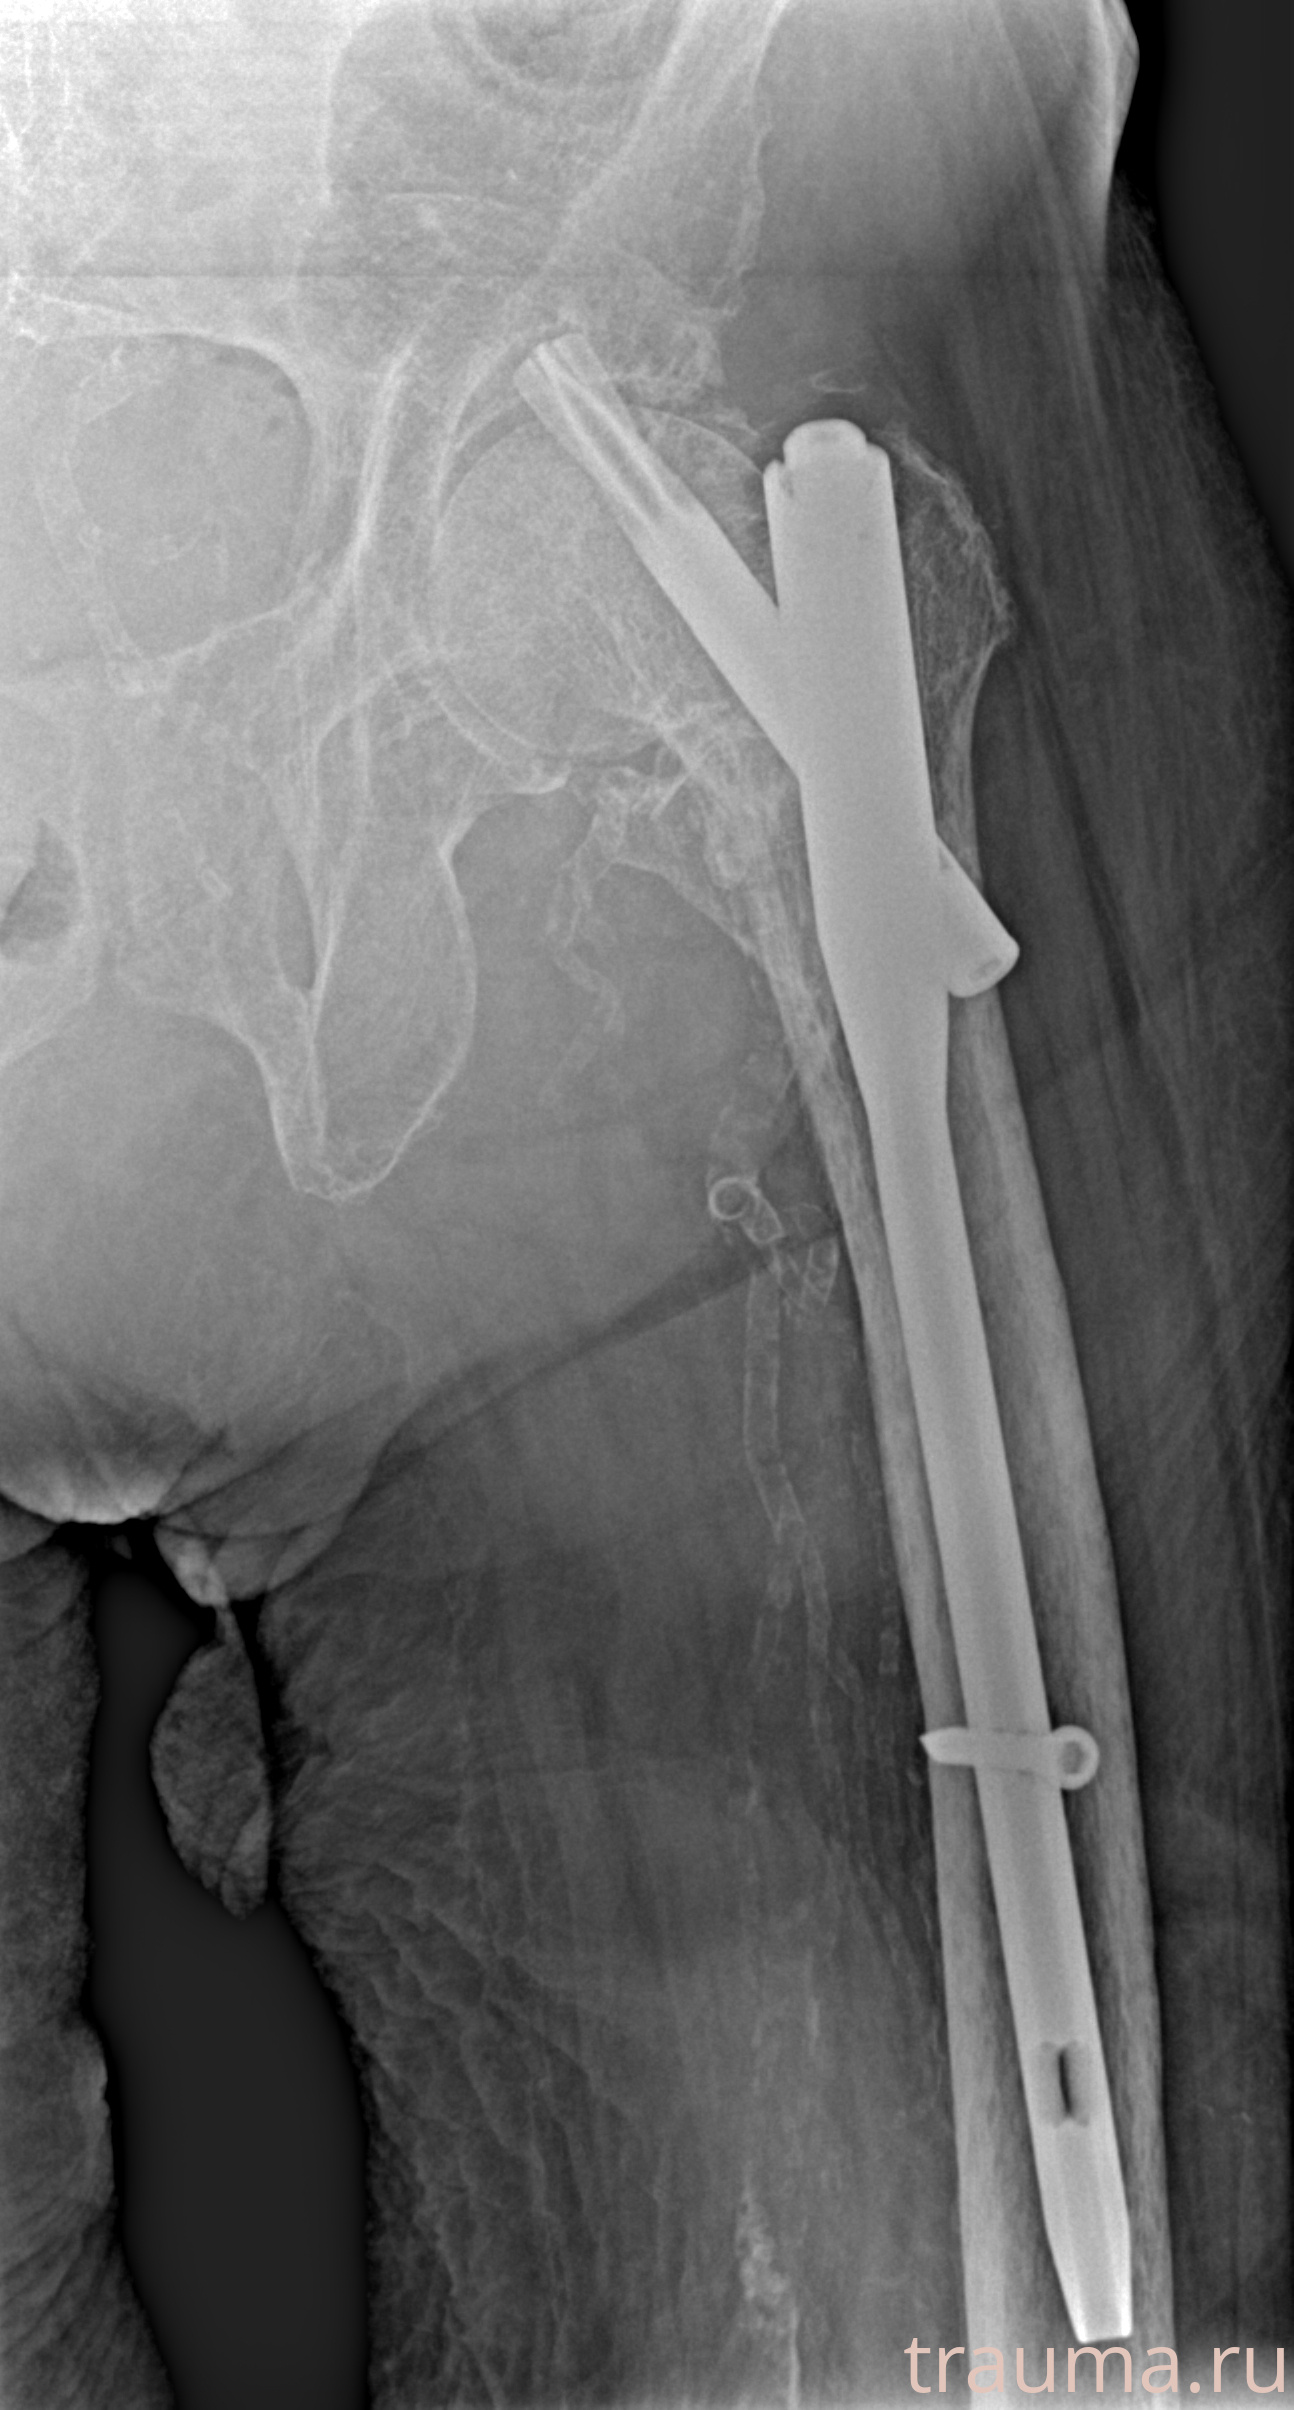

Рентген на дому: по вашему адресу приезжает врач-рентгенолог, травматолог-ортопед с мобильным рентгеновским аппаратом, проводит диагностику травмы или заболевания, делает необходимые рентгенограммы, дает рекомендации по дальнейшему лечению. Получить качественные снимки в домашних условиях возможно благодаря уникальной методике, разработанной МосРентген Центром для института  Склифосовского